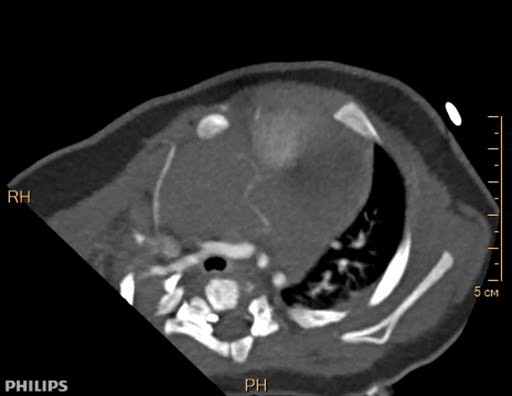

Опухоли сердца у детей — гетерогенная группа новообразований, произрастающая из тканей и оболочек сердца. Опухоли могут развиваться из любых тканей сердца и возникать в любом детском возрасте. У плода они могут быть обнаружены с помощью фетальной эхокардиографии, начиная с 16-20 нед. внутриутробного развития.

Все опухоли сердца несут потенциальную опасность возникновения смертельно опасных осложнений - сердечной недостаточности, аритмий, перикардита, тампонады сердца, системных эмболий.

Выполняется трансторакольное ЭХОКГ исследование, которое позволяет заподозрить локализацию и размер опухоли, ее соотношение с другими анатомическими структурами сердца.